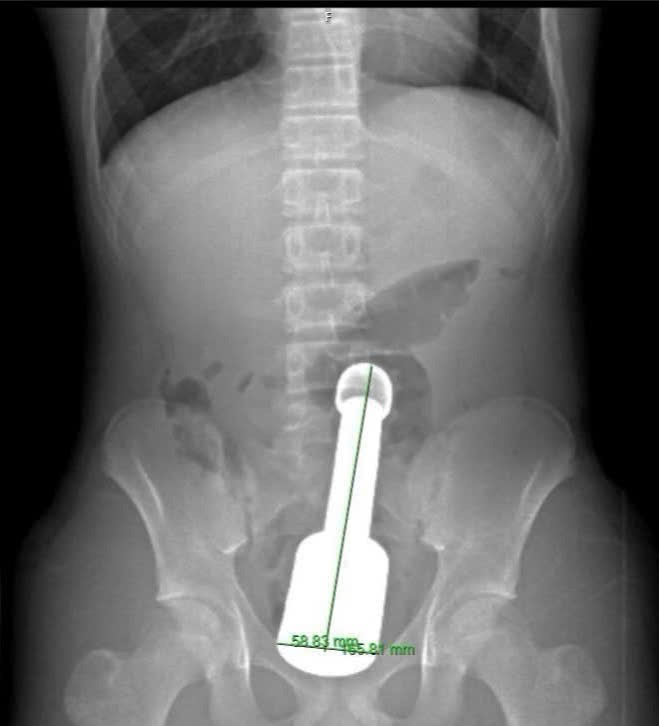

Patient N.K.N (15 years old, Ha Dong, Hanoi) was admitted to the hospital at night with symptoms of severe pain and tightness in the lower abdomen. X-ray results showed that a large metal foreign object was located deep in the rectum, causing compression of the pelvic organs and posing a risk of serious complications if treated in time.

After a comprehensive assessment, the surgical team decided to remove the foreign object through the anus to avoid open abdominal surgery, reduce the risk of injury and preserve the patient's function. However, the intervention process faced many challenges when the foreign object was a pestle about 18 cm long, 6 cm in diameter - almost equal to the maximum limit of the anal sphincter in adolescents. The foreign object also created a "vacuum effect" causing it to be drawn tightly into the intestinal lumen.